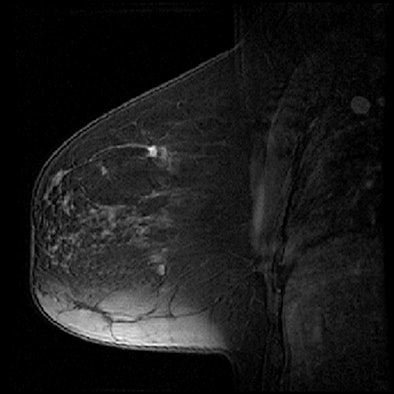

| Contrast-enhanced 1.5-tesla MR images show a patient at low risk of breast cancer recurrence (above) and a patient at high risk (below). |

Daye and colleagues analyzed seven characteristics of the tumors as seen on MRI: size, multifocality, shape, margin morphology, enhancement amount, enhancement kinetics, and associated nonmass enhancement.

Daye and colleagues found that of the MRI-based tumor features, multifocality and lesion size were most significant in predicting the recurrence risk categories on the Oncotype DX assays (p < 0.05). Using three of the MRI tumor features, including multifocality and lesion size, produced the most significant agreement in predicting the Oncotype DX recurrence risk categories (kappa = 0.41, p = 0.01).

Based on the results, the researchers concluded that breast MRI tumor features could help predict breast cancer recurrence, with multifocal and larger lesions appearing to increase risk. When combined in a linear discriminant analysis model, the tumor features can predict the risk category of the Oncotype DX assay, according to the group.